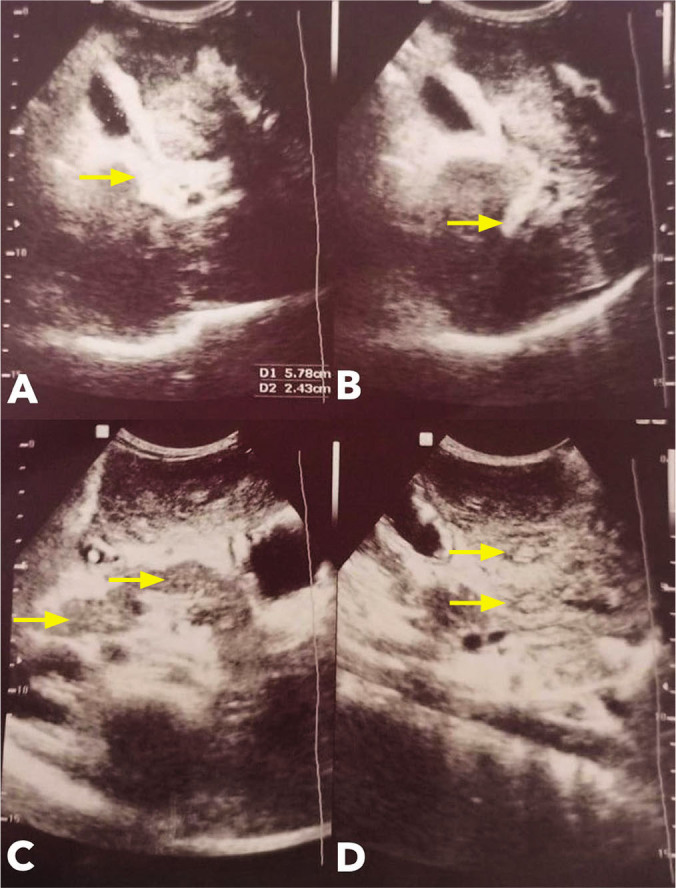

Schistosomiasis, a snail-borne disease caused by infection with a trematode parasite of the genus Schistosoma, is one of the most neglected tropical diseases in the world. One of its rare complications is hepatosplenic schistosomiasis which ultimately leads to fibrosis and presinusoidal portal hypertension. We report a case of a 13-year-old Filipino male from Quezon City with previous one year residence in the endemic island of Leyte, presenting with melena. Diagnostic work-up revealed hepatosplenomegaly and periportal fibrosis with multiple hepatic nodules on ultrasound, positive Schistosoma japonicum eggs on Kato-Katz stool examination technique, and findings of esophageal varices on upper endoscopy. The patient was managed with praziquantel, propranolol, and endoscopic rubber band ligation of the esophageal varices, with note of resolution of bleeding, and improvement on sonographic liver findings. The degree of liver fibrosis from schistosomiasis is affected by poorly understood mechanisms which affect its severity, progression, and complications, regardless of biosocial factors including egg burden and duration of parasite exposure. This is the first case report on a Filipino adolescent to document significant interval improvement, within four weeks of treatment, of the characteristic fibrotic pattern in hepatosplenic schistosomiasis. Hepatosplenic schistosomiasis is still often missed out as the diagnosis in patients who consult with common symptoms, and high index of suspicion is recommended for those with history of residence in endemic areas. Likewise, treatment focusing on parasite eradication can aid in promptly addressing the resulting fibrosis and its complications.